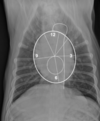

What structures live from 12 o'clock to 6 o'clock?

12 o'clock: aortic arch 1-2 o'clock: main pulmonary artery 3 o'clock: left auricle 3-6 o'clock: left ventricle

38

What structures live from 6 o'clock to 11 o'clock?

6-9 o'clock: right ventricle 9-11 o'clock: right atrium